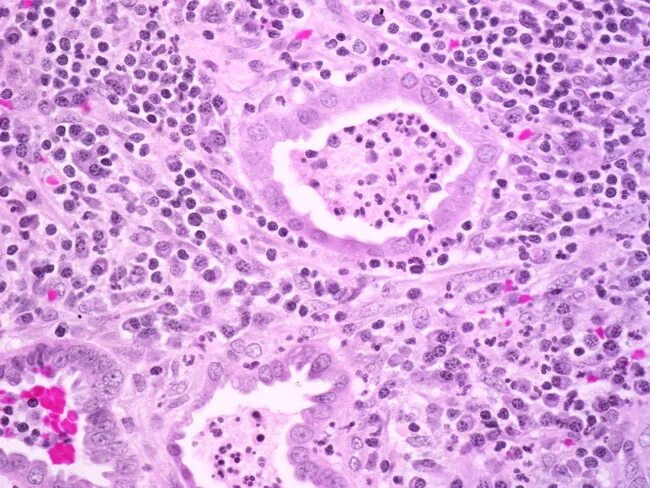

Эндометрит гистология